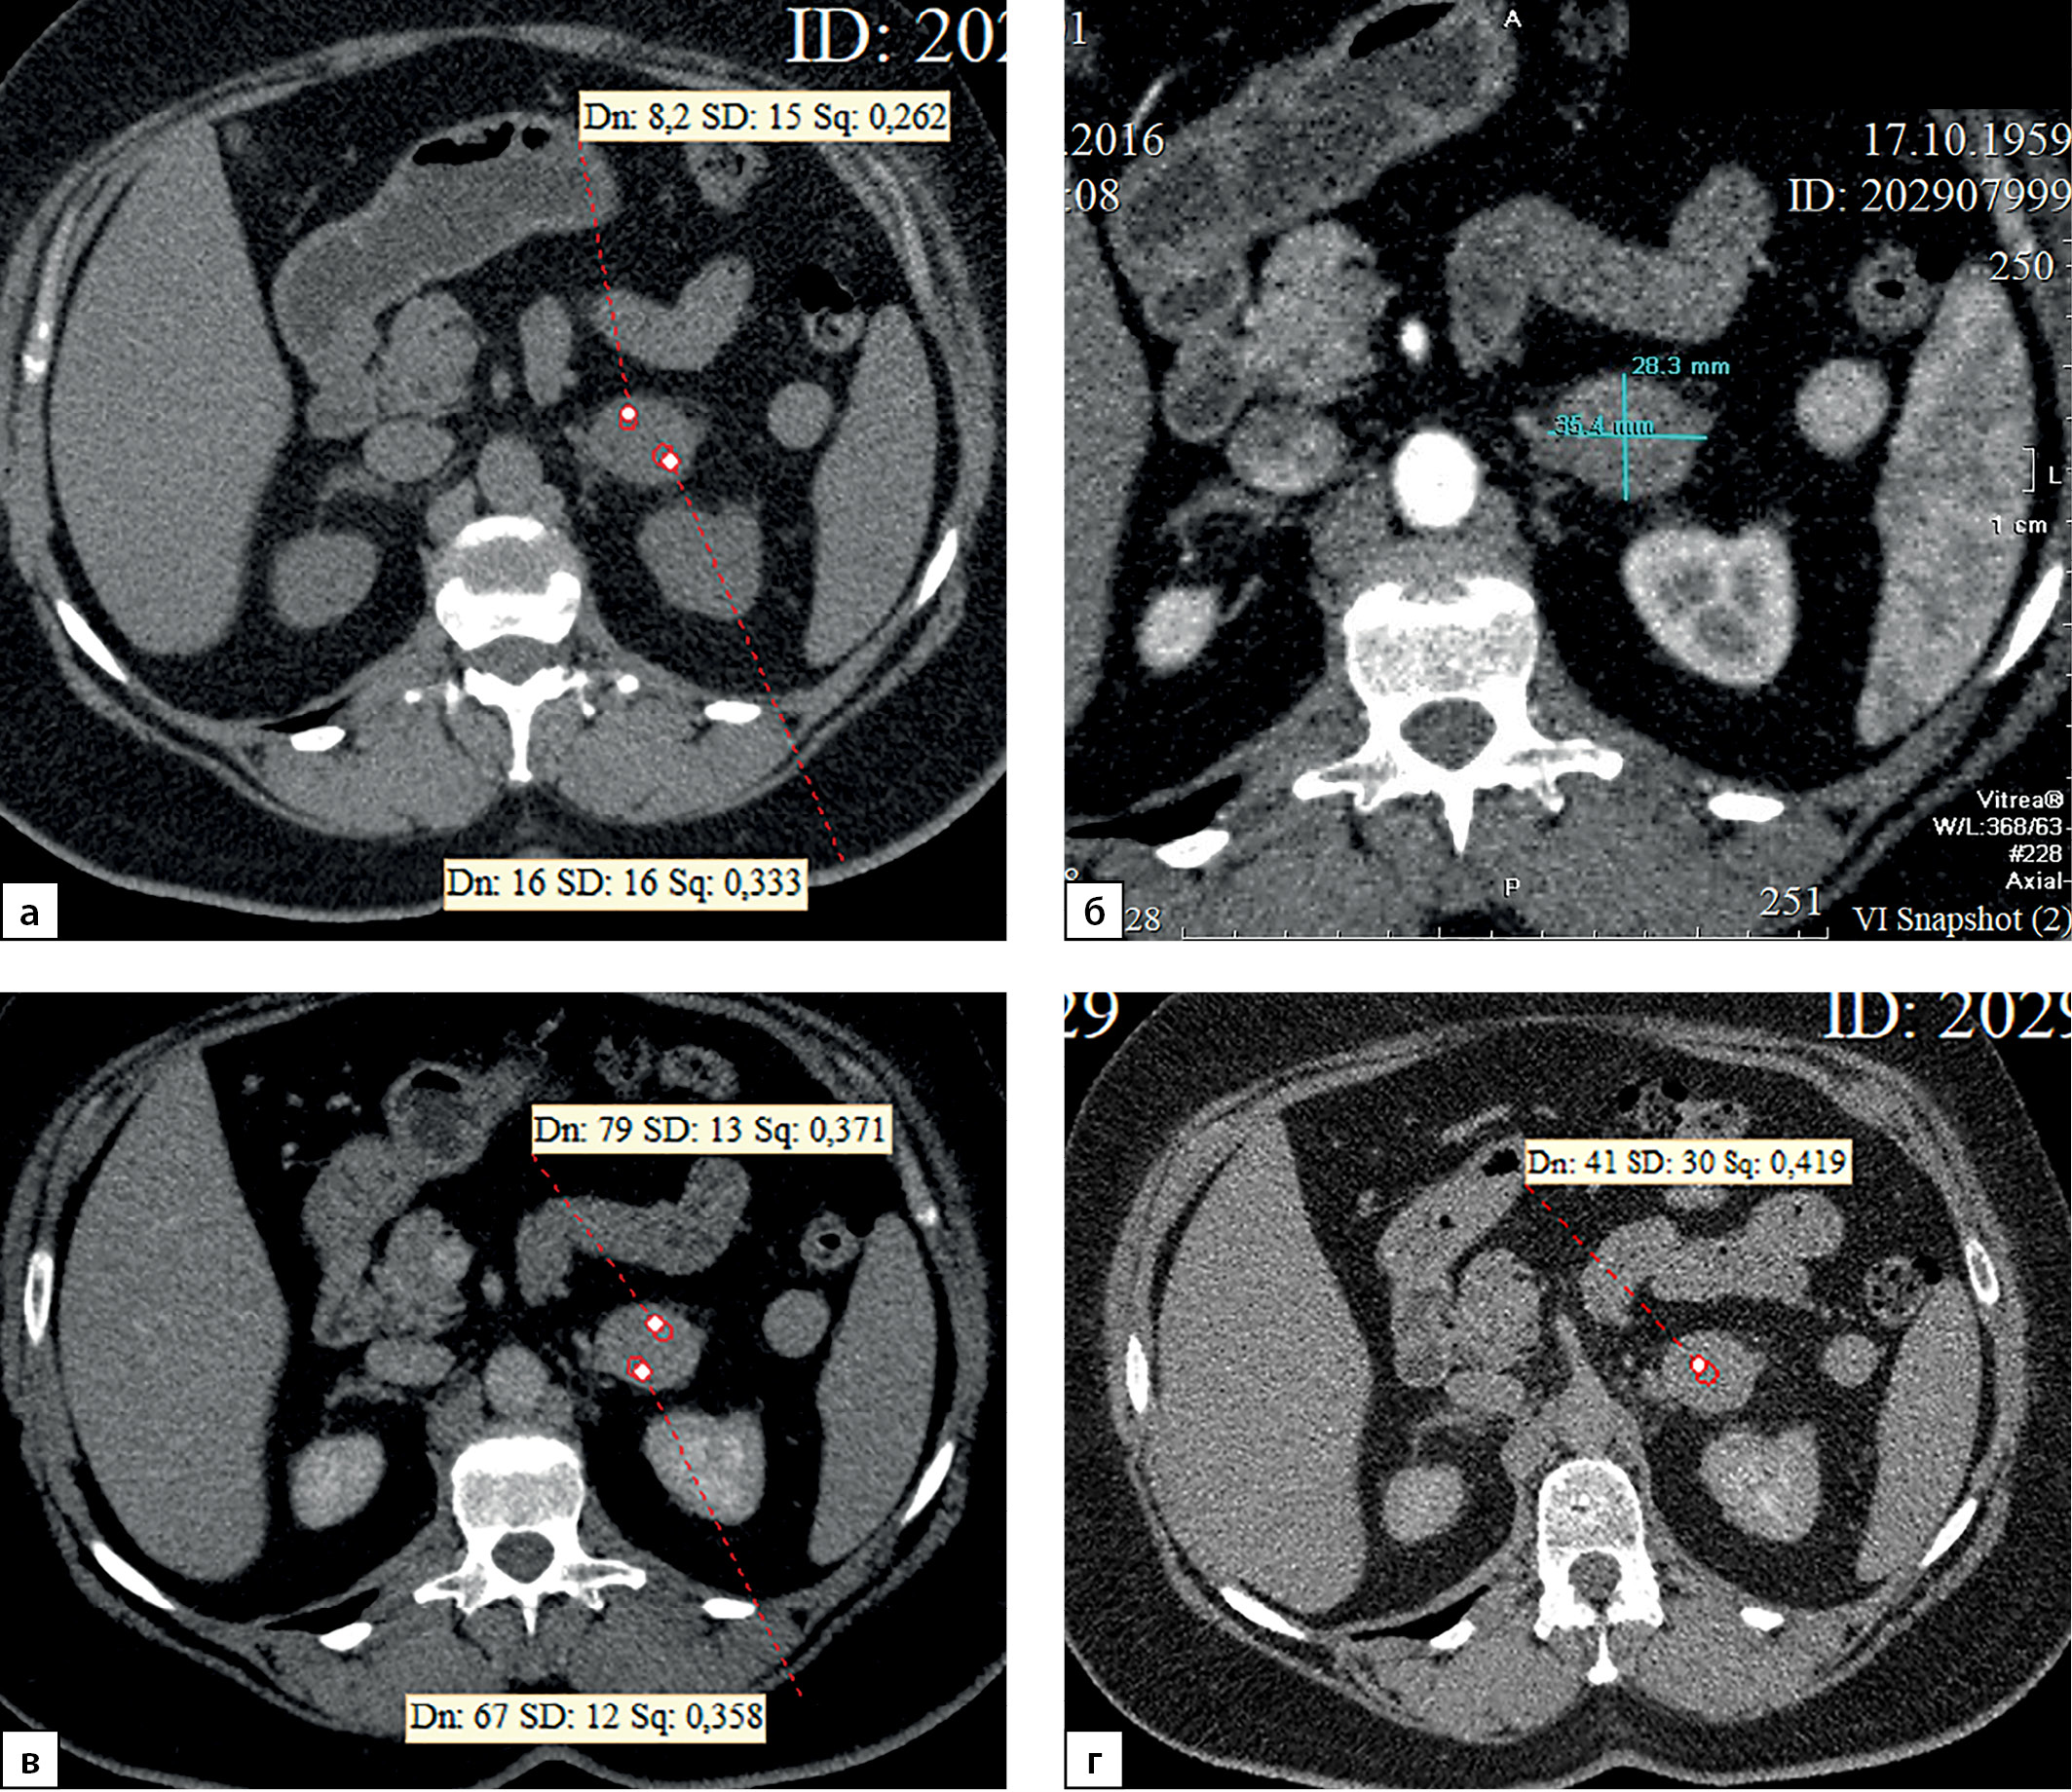

В 10% наблюдений (7 случаев) при КТ выявлены признаки инвазии опухоли в прилежащие анатомические структуры. Подобная ситуация встречается лишь у пациентов с опухолями большого размера. В 5 случаях при КТ определяется врастание опухоли в нижнюю полую вену (рис. 13), при этом в двух наблюдениях, кроме поражения вены (рис. 14), отмечена инвазия в ткань печени (1) и почки (1). В двух наблюдениях АКР распространялся на почку (1) и поджелудочную железу (1). В 8,6% наблюдениях (6 случаев) выявлялось увеличение забрюшинных лимфоузлов.

Рисунок 13. Компьютерные томограммы пациентки С., 24 лет, с гигантской опухолью правого надпочечника (165 мм), вызвавшей тромбоз нижней полой вены: а — изображение реформатированное в косой корональной плоскости, венозная фаза сканирования, опухолевый тромб в нижней полой вене (стрелки), пролабирующий в правое предсердие (стрелки); б — изображение реформатированное в косой сагиттальной плоскости, венозная фаза сканирования; в — венозная фаза, аксиальная плоскость.

Figure 13. Computed tomography of patient S., 24 years old, with a giant tumor of the right adrenal gland (165 mm), which caused thrombosis of the inferior vena cava: a — image reformatted in an oblique coronal plane, venous phase of scanning, tumor thrombus in the inferior vena cava (arrows) , prolapsing into the right atrium (arrows); b — image reformatted in the oblique sagittal plane, venous phase of the scan; c — venous phase, axial plane.

Рисунок 14. Компьютерные томограммы пациентки М., 41 года, с крупной опухолью правого надпочечника размерами до 90 мм: а — артериальная фаза постконтрастного сканирования, диффузно неравномерное накопление контрастного препарата, зона гиперперфузии в компримированном отделе правой доли печени; б — изображение, реформатированное в косой сагиттальной плоскости, венозная фаза сканирования; образование широко прилежит, деформирует нижнюю полую вену (стрелки). Во время операции потребовалось выполнение пластики нижней полой вены вследствие инвазии в последнюю опухоли надпочечника.

Figure 14. Computed tomography of patient M., 41 years old, with a large tumor of the right adrenal gland up to 90 mm in size: a — arterial phase of post-contrast scanning, diffusely uneven accumulation of the contrast agent, hyperperfusion zone in the compressed section of the right lobe of the liver; b — image reformatted in the oblique sagittal plane, venous phase of the scan; the mass is widely adjacent, deforming the inferior vena cava (arrows). During the operation, plastic surgery of the inferior vena cava was required due to invasion into the last tumor of the adrenal gland.